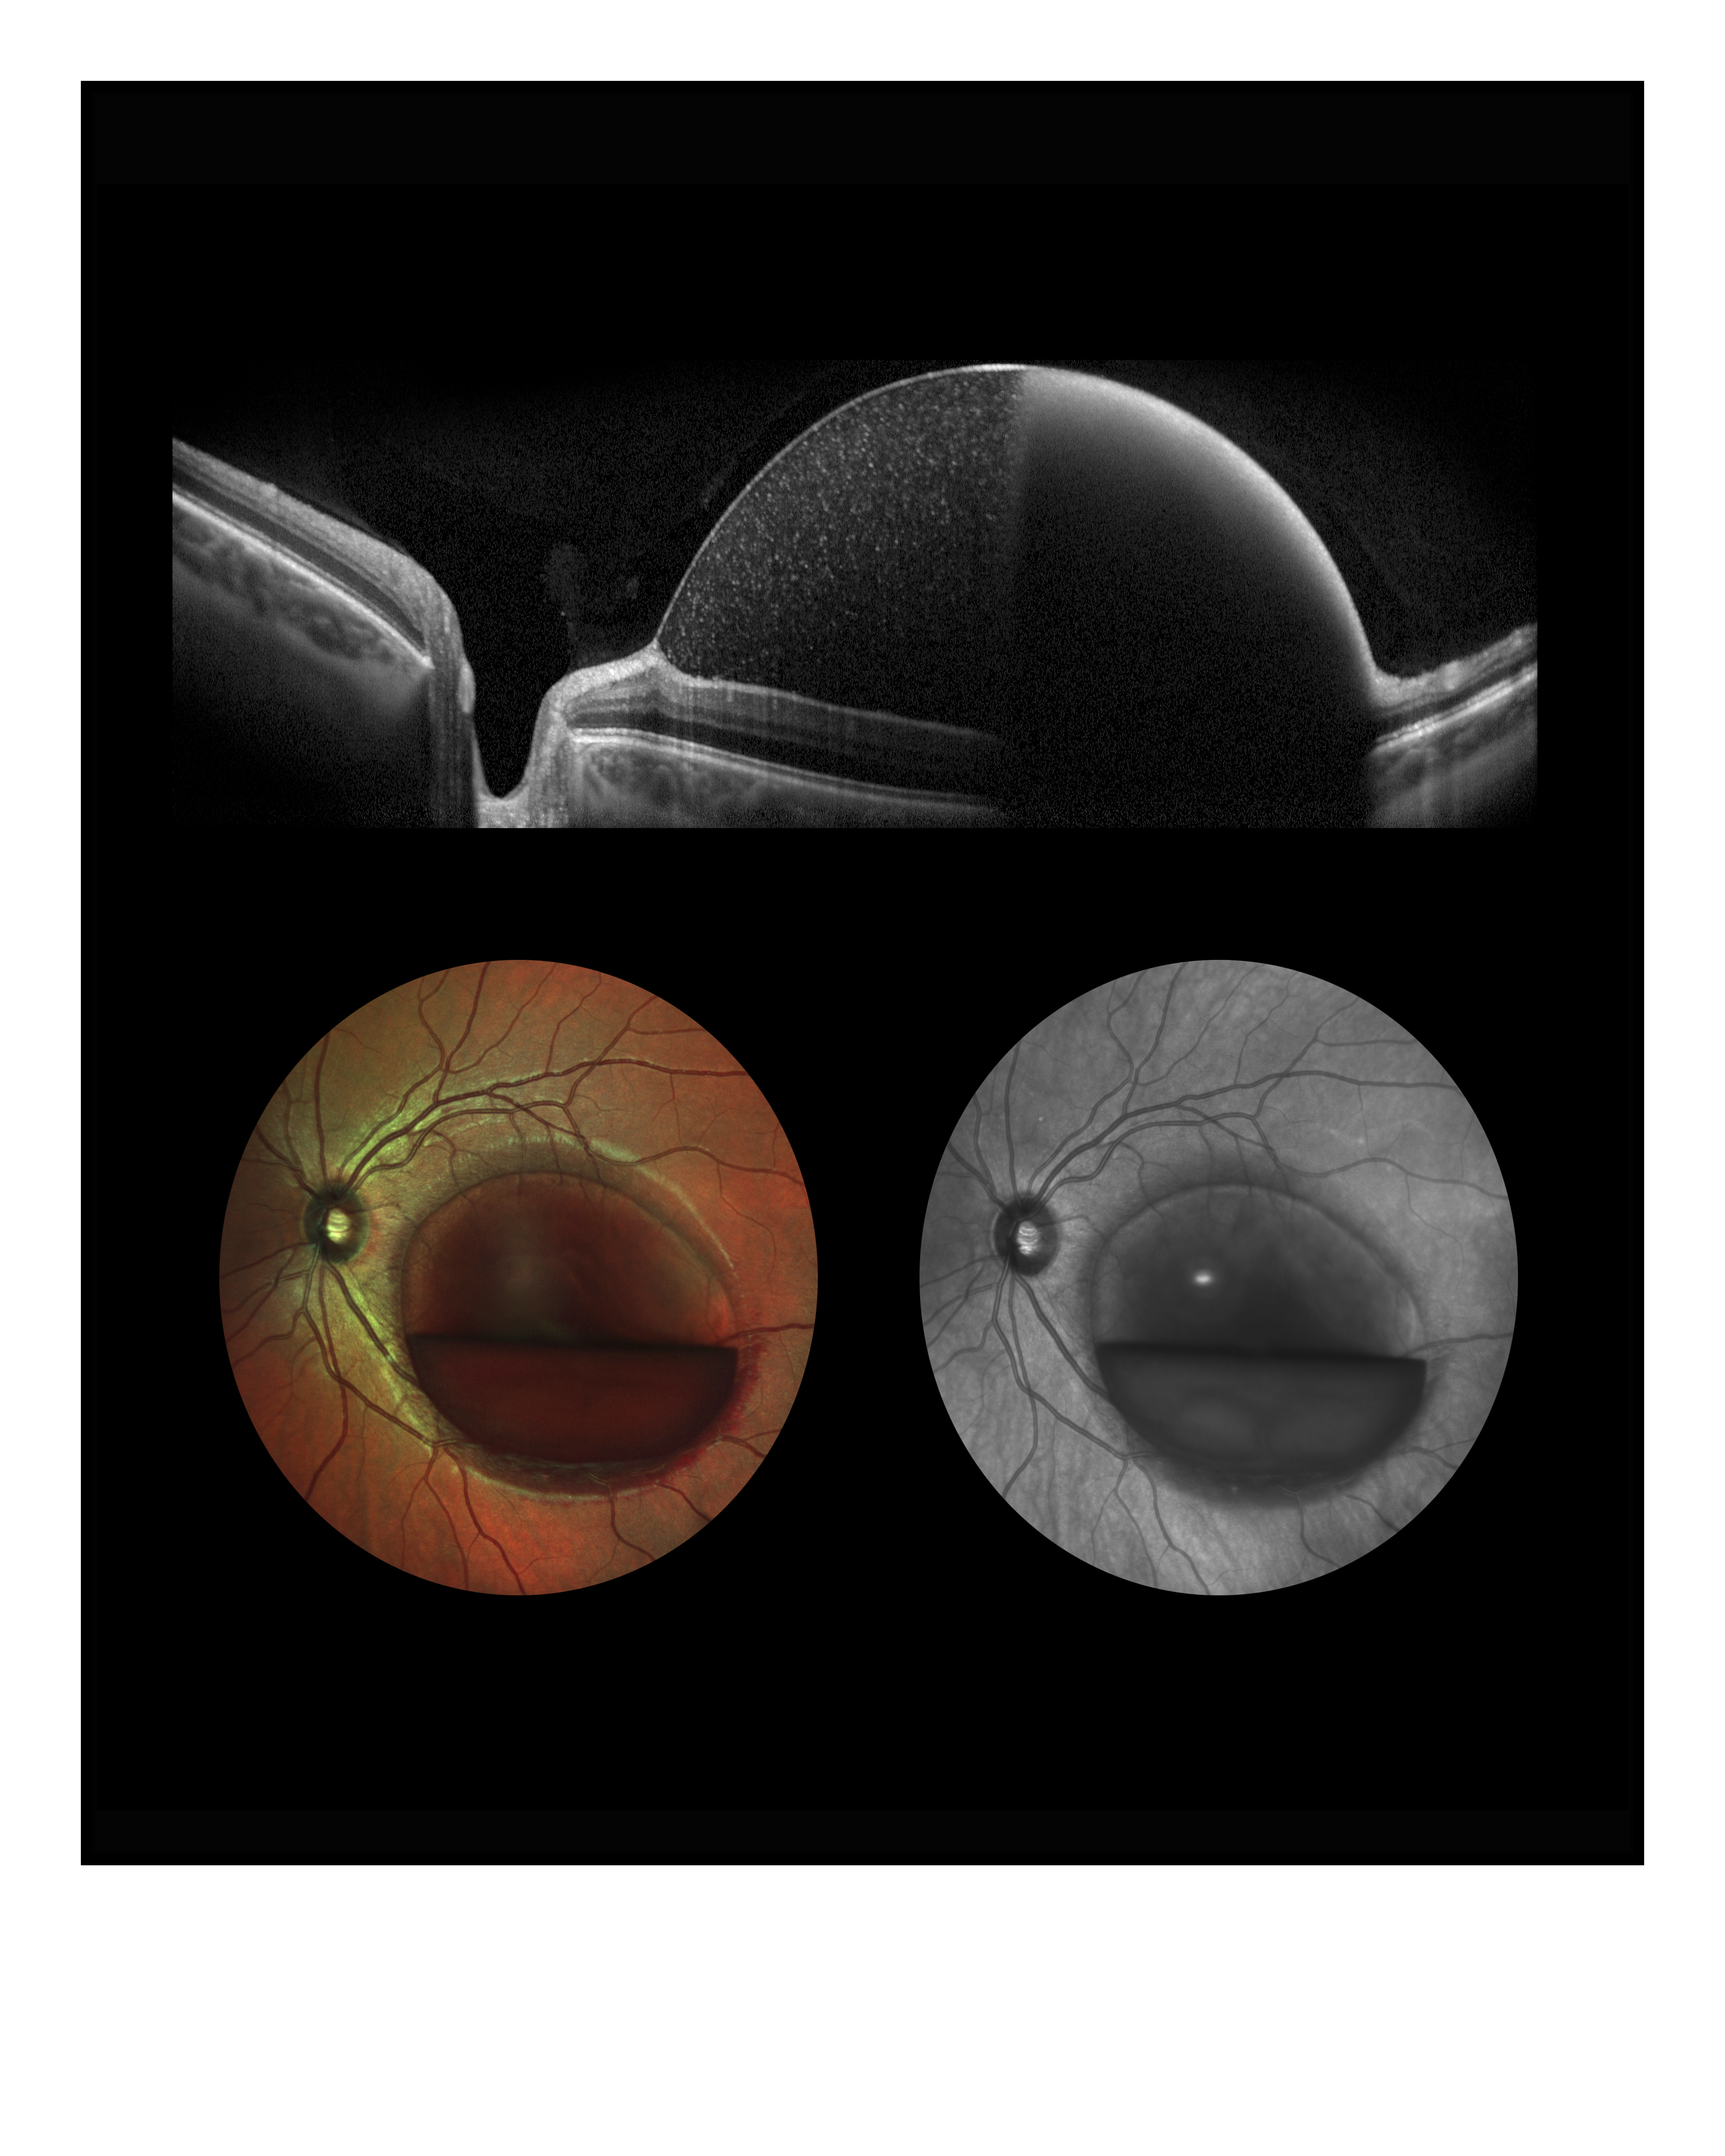

Preretinal Hemorrage Presented by Clint Downer, OCT-C This photograph received First Place in the category "Cross Categories" and was displayed in the 2024 OPS Exhibit. Filed Under Retina OPS Photo